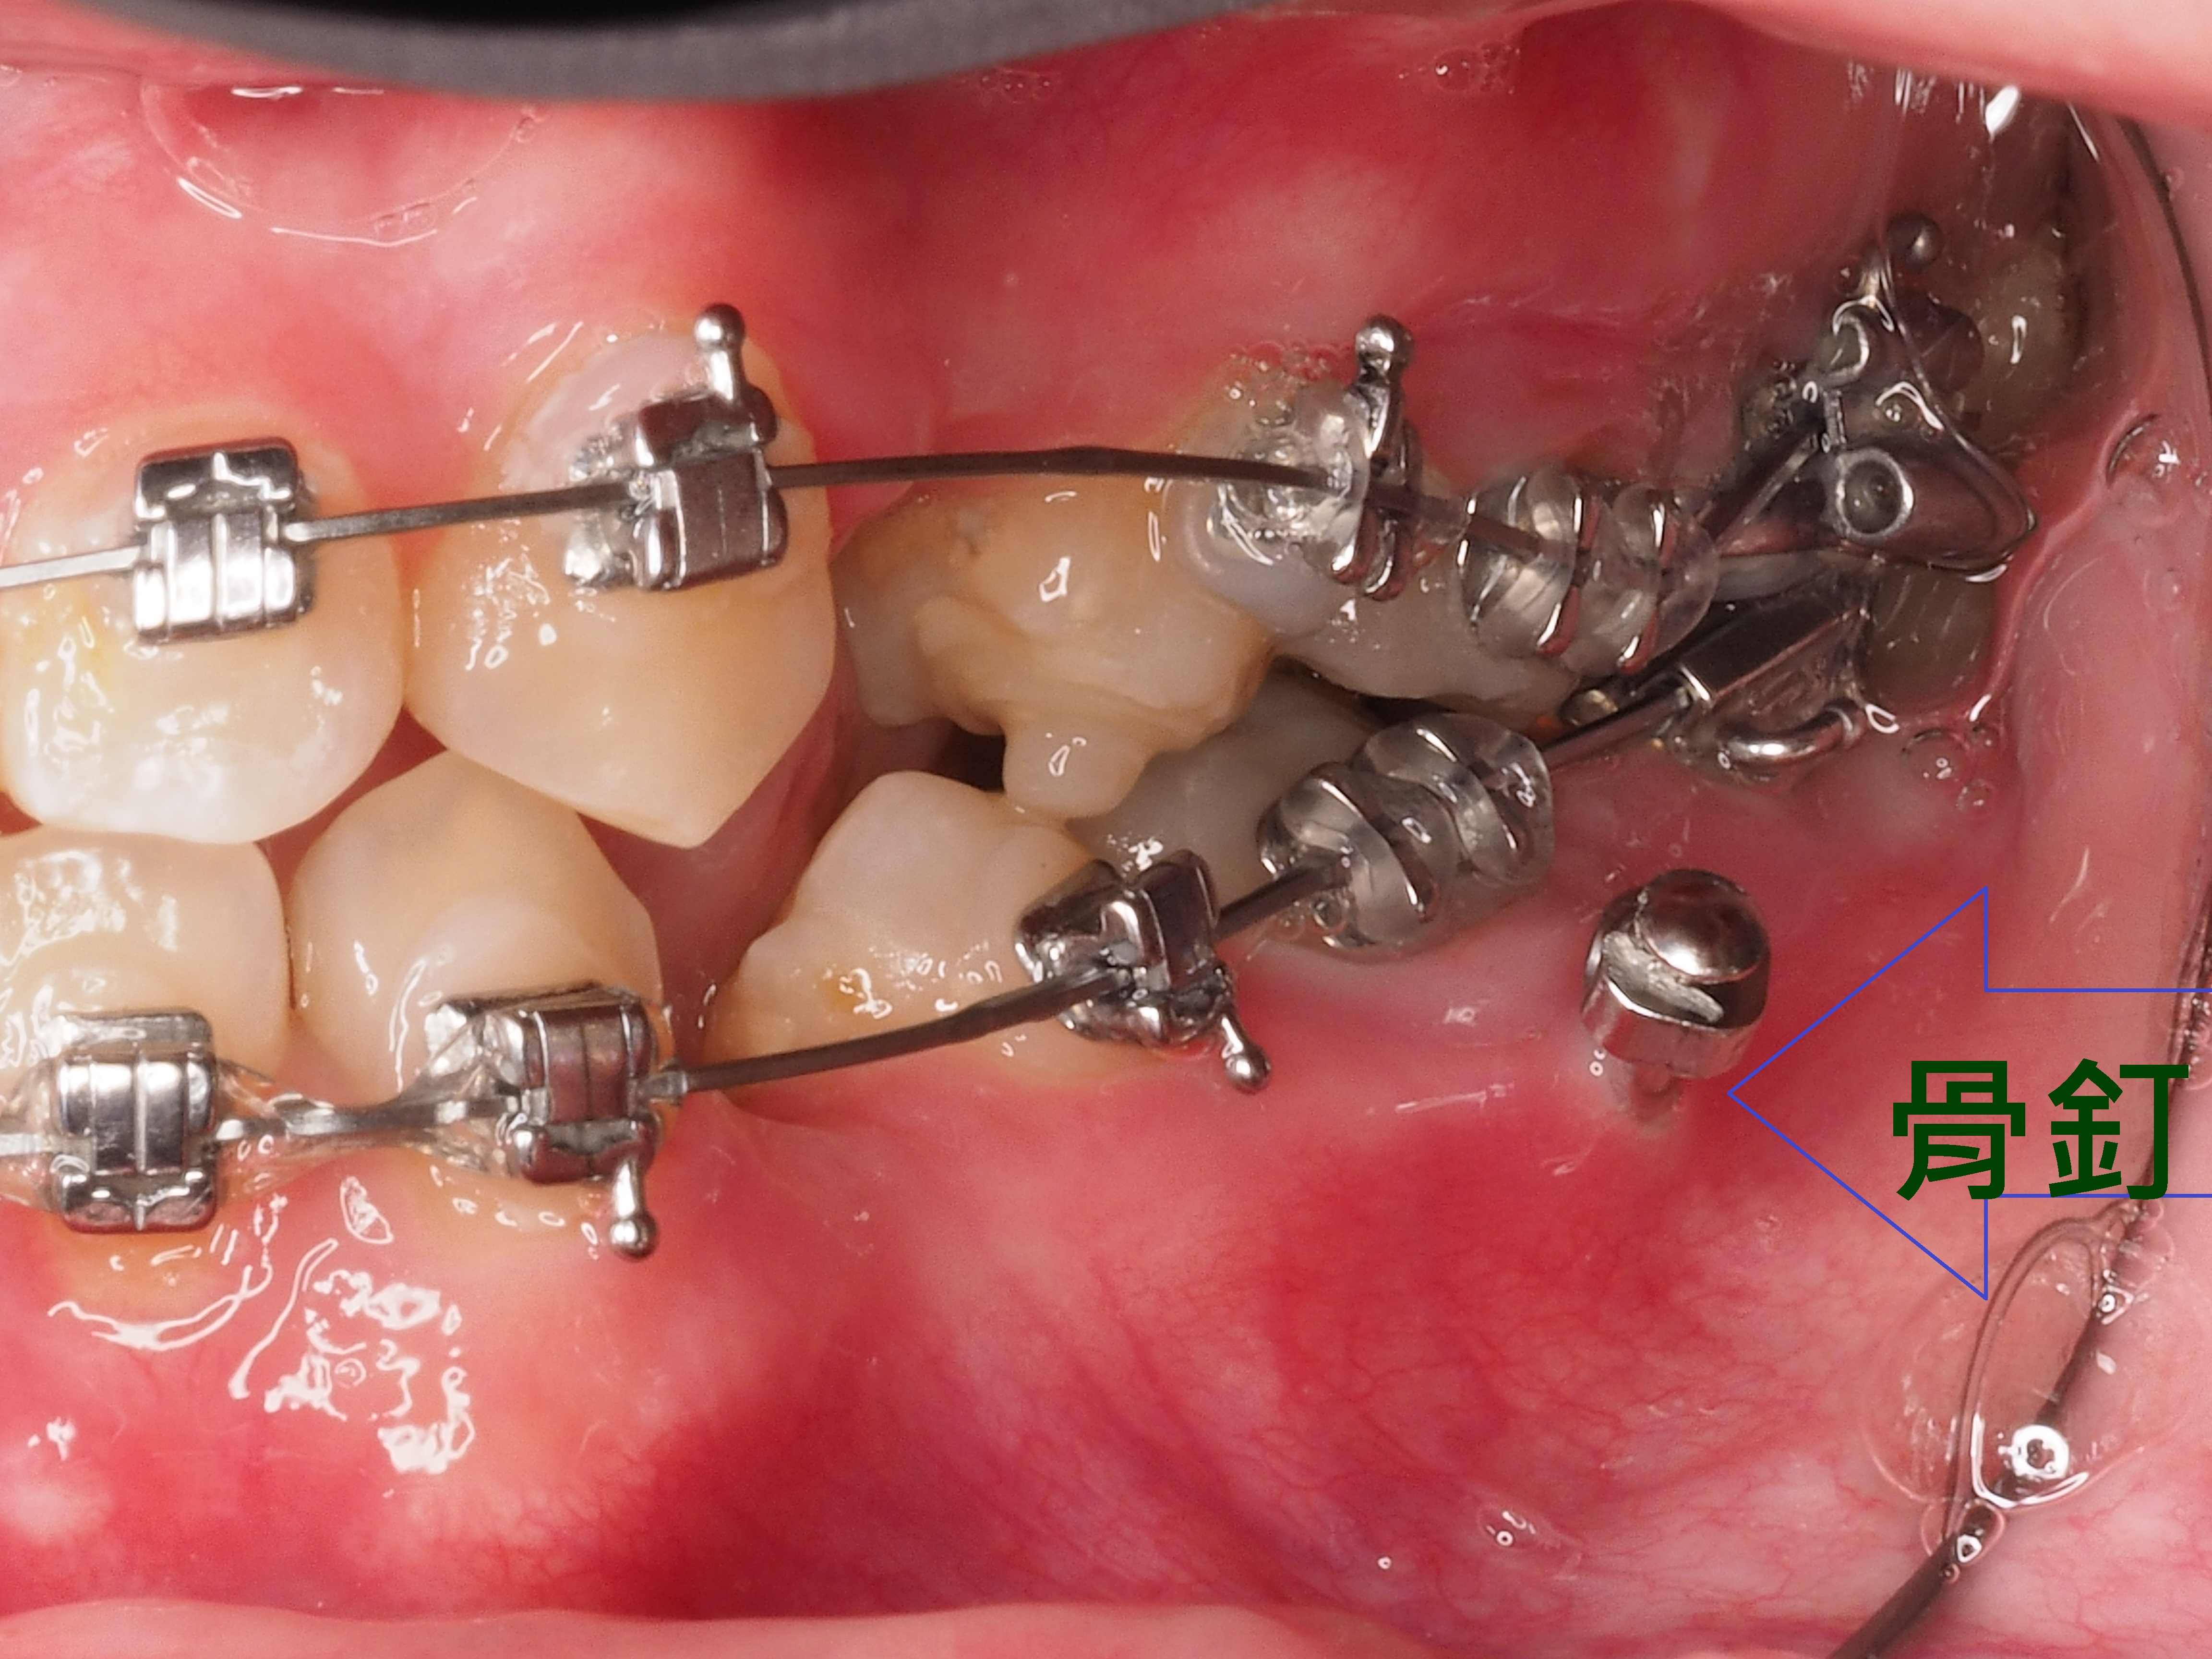

患者牙齒凌亂虎牙外暴大大影響外觀,並造成清潔不易、蛀牙、牙齦發炎等問題,透過醫師矯正評估分析建議矯正計畫內容包含拔牙、放置迷你螺絲(骨釘)等步驟,將原本凌亂外暴的虎牙歸位,改善咬合使發音更清晰,咀嚼效率更好,大幅改善清潔困擾,使日常刷牙及使用牙線清鬆有效率。

3.拔牙與骨釘:為騰出空間進行矯正,需要拔牙;骨釘用於輔助移動牙齒,初期可能會有異物感,但通常很快能適應。(下兩圖)

拔牙後放骨釘關閉空間原理與優點:

1.骨釘是植入在骨頭中的支撐點,提供穩定的錨定力量,確保牙齒移動的方向不受影響。

2.傳統矯正中移動牙齒可能造成其他牙齒跟著移動,使用骨釘可以精準控制牙齒的移動方向,讓拔牙後的縫隙能有效且正確地關閉。

3.骨釘可以大幅提升牙齒移動的效率,可能縮短矯正療程時間。

4.除了關閉拔牙空間,骨釘還能應用於骨性暴牙、嚴重深咬等情況,讓治療範圍更廣。